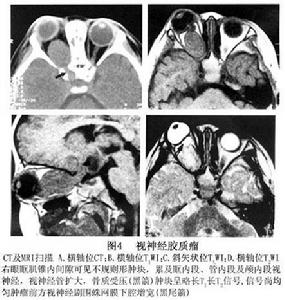

圖4 視神經膠質瘤鑑別診斷

影像學鑑別診斷:①視神經腦膜瘤:好發於成年女性,視力障礙,多在眼球突出之後 視神經鞘腦膜瘤可為偏心性,CT值較高,可伴有斑點、環形或不規則的鈣化,MRI 檢查T1WI、T2WI均呈中等信號,CT或MRI增強後可見“軌道征”;②視神經炎:臨床上表現視力急劇下降,可伴有眼球轉動時疼痛和眼眶深部脹痛等症狀。MRI表現為視神經瀰漫性增粗 一般不形成軟組織腫塊,T1WI視神經信號減低,T2WI信號增高,STIR呈高信號,增強後可有強化,以增強掃描聯合脂肪抑制序列顯示最佳, 可為多發性硬化的一種改變,MRI顯示腦室周圍硬化斑塊,則可確定本病。

另外,主要和一些能夠引起視神經增粗的疾病區別,如:炎性假瘤、腦膜瘤等。炎性假瘤常有炎症的表現,且視神經增粗的形狀常呈不規則增粗,所以與膠質瘤容易鑑別。腦膜瘤多見於成年人,視神經增粗的形狀各異,邊界不規則, 臨床鑑別有困難時應進行活檢證實診斷。